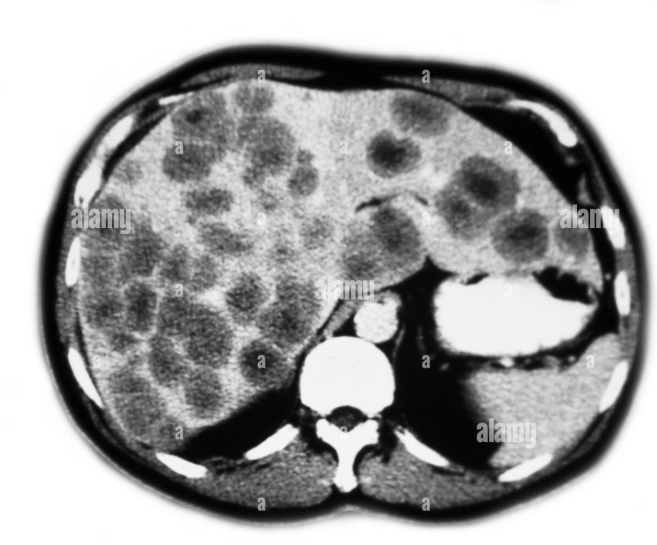

Paciente de 60 años de edad con una masa en colon de 6 meses de evolución. La paciente presenta hematoquecia y perdida de peso.

Se realizó una biopsia de la neoplasia y se observan  los siguientes hallazgos microscópicos.

También se realizaron estudios de imagen a nivel de la cavidad torácica y abdominal y se observaron múltiples lesiones hepáticas y pulmonares intraparenquimatosas.

Del siguiente caso podemos afirmar lo siguiente excepto.